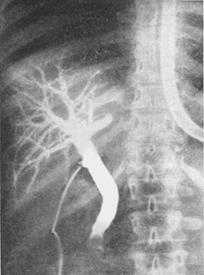

Необходимым условием при выполнении данной операции является проведение интраоперационной холангиографии через пузырный проток под рентгенологическим контролем для исключения «немых» камней в холедохе.

Интраоперационная холангиография

Конкремент в дистальный отделе холедохе